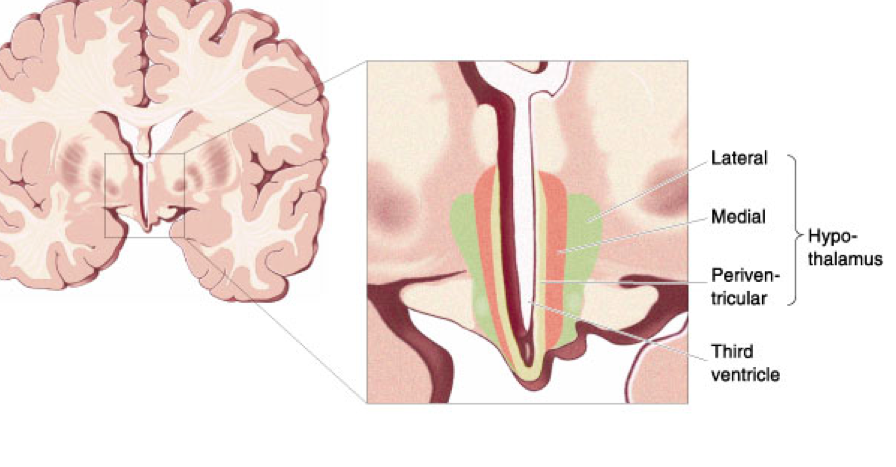

What are the 3 principal zones of the hypothalamus?

upstream= take off your shirt get out of the sun etc

What do lateral and medial zones of the hypothalamus do?

-behavioural patterns

What does the periventricular zone of the hypothalamus do?

-neurosecretory